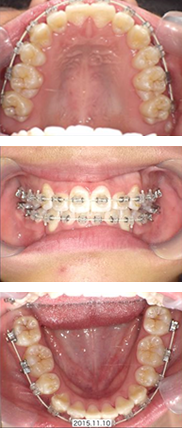

全体矯正症例

16才 女性

顎の成長が終了してから抜歯を行い、スペースを確保してそこにゆっくりと歯を移動させていきます。

歯並びも咬み合わせも整い、無事に矯正装置を外すことができました。

矯正前

矯正中

矯正後